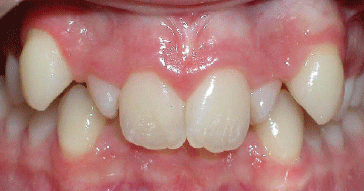

Class II Div I |